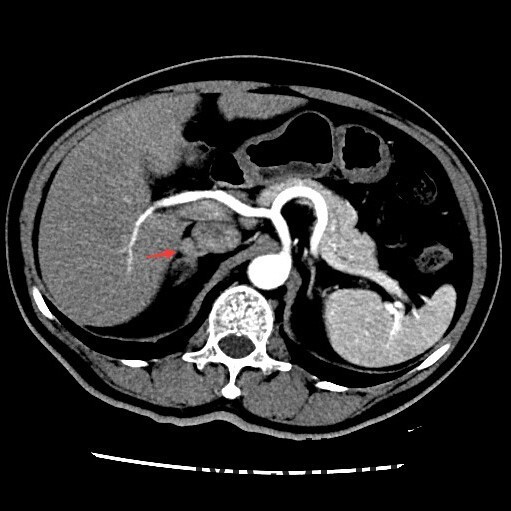

查体::血压:140/80mmHg。双肾区无红肿、隆起,无叩痛,双侧肋脊点、肋腰点无压痛。 辅查:双肾上腺CT提示:右侧肾上腺结节,考虑腺瘤可能性大,右侧小囊肿,肝内多发囊肿。

随访:术后病理示:考虑为肾上腺皮质腺瘤。 讨论:肾上腺腺瘤是来源肾上腺皮质的腺瘤,根据临床表现不同,临床分为无功能性腺瘤、功能性腺瘤(又分为Cushing腺瘤和Conn腺瘤),本例患者具有乏力、低血钾和高血压等醛固酮增多症表现,应属于Conn腺瘤。该类腺瘤一般表现为肾上腺区的孤立性小肿块,边界清楚,大小一般不超过2cm,由于富含脂质,CT平扫密度接近于水样密度,增强扫描轻度强化,本例的CT影响表现基本符合。